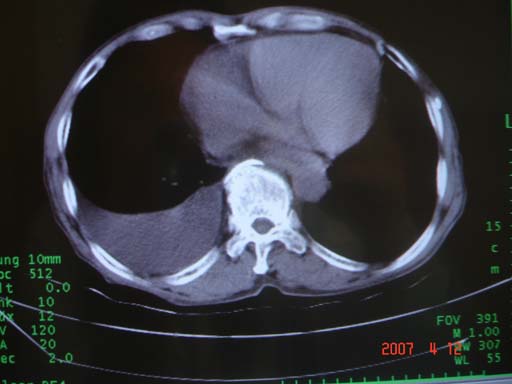

帮我 看看。男77岁咳嗽咯血2月发热2周!病人一般情况可 口痰为鲜红,有点象洗肉水(我看见他吐的痰了)

为何只有这么几幅图像?连纵隔窗都没有。但我发现上叶支气管显示不清,再加上年纪大,咯血等症状,恶性肿瘤首先得考虑。

考虑右肺新生物伴右中上肺阻塞性肺炎及含气不良,右侧胸腔积液。建议痰与纤支镜检查

考虑右侧中央型肺癌伴中上肺阻塞性肺炎、不张,胸腔积液。,建议支纤镜检查。

考虑:右上肺癌伴中上叶炎症,右侧胸腔积液。